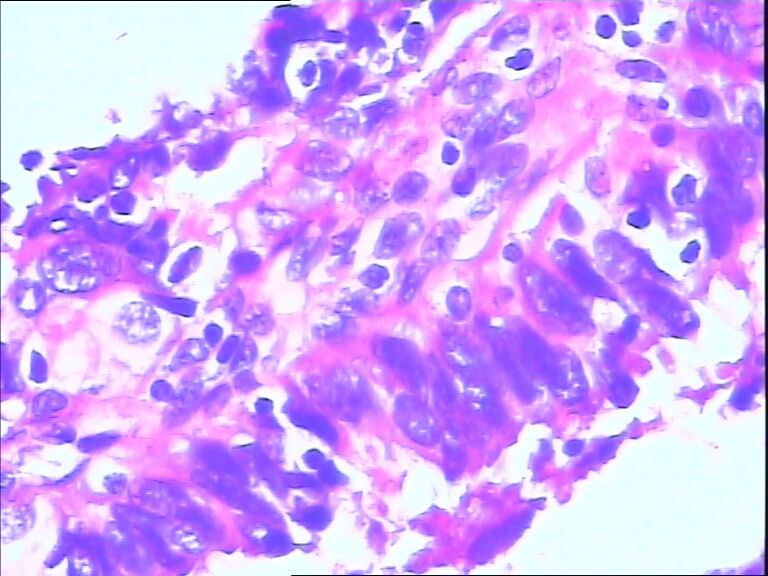

女,43y

左输卵管积液

输卵管长4.5cm;直径:0.8cm

• 请教:输卵管!图2

图2

输卵管增生性上皮病变。

慢性炎伴上皮增生

良性,炎症改变

考虑炎症